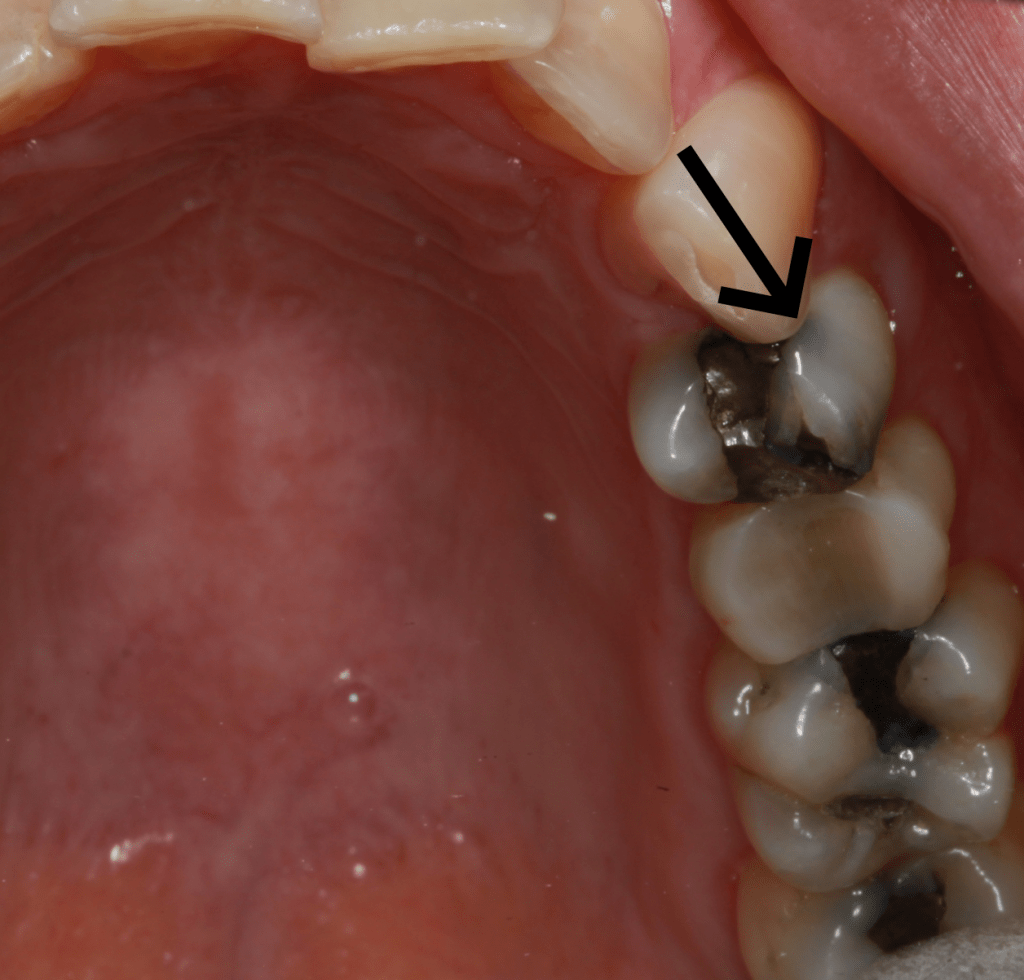

Amalgam has the ability to stain surrounding tooth structure by leaching corrosion products into the dentin tubules. The tooth may also be darker because of the dark filling and the translucent properties of a tooth. Elective replacement of the filling may be warranted for esthetic purposes.